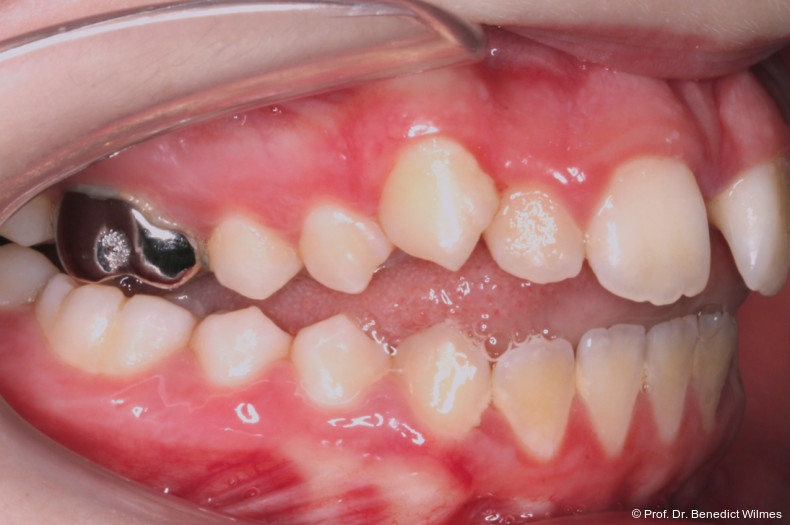

Nach dieser Rentionszeit wurde die Hybrid Hyrax entfernt und ein Scan zur Herstellung der Molarenintrusionsapparatur (digitale Mause­falle) durchgeführt. Die beiden Miniimplantatköpfe lassen sie dabei sehr gut scannen, so­genannte Scan-Bodies sind in der Regel nicht mehr notwendig. Die digitale Mousetrap-­Appa­ratur besteht aus zwei Teilen (Abb. 6):

Der erste Teil ist ein TPA (bzw. Horseshoe-­Arch) mit Shells auf den ersten oberen Molaren sowie mesialen und distalen Extensionen auf den zweiten Prämolaren und den zweiten Molaren. Der TPA besitzt zudem kleine Extensionen zur späteren Befestigung von Power­chains oder NiTi-Federn. Zwischen TPA und palatinaler Mukosa sollte ausreichend Abstand eingeplant werden, um Druckstellen und Irritationen nach erfolgreicher Intrusion zu vermeiden. Die zweite Struktur wird üblicherweise an zwei oder drei Miniimplantaten im Gaumen fixiert. Sie umfasst ein H-förmiges Gerüst mit kleinen Extensionen zur Befestigung der Powerchains oder NiTi-Federn. Der biomechanische Kraftvektor ist auf die kranial (superior) positionierten Miniimplantate mit dem H-Gerüst ausgerichtet. Die erforderliche Intrusionskraft wird mit mindestens 200 g pro Seite avisiert. Die Kraft kann sowohl mittels Zugfedern oder elastischen Ketten appliziert werden, klinisch empfehlenswerter erscheinen jedoch Federn, da sie nicht bei jedem Termin gewechselt werden müssen. Aufgrund der starren Konstruktion des TPA werden Nebenwirkungen wie Kippungen der posterioren Zähne während der Kraft­applikation verhindert. Zur zusätzlichen Verankerung wurde in diesem Fall ein posteriores Benefit Direct-Implantat inseriert. Mittels der Mausefalle konnte der offene Biss erfolgreich innerhalb von acht Monaten korrigiert werden (Abb. 7a–f).